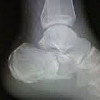

Рентгенография пяточной кости

Рентгенография пяточной кости. Метод изучения этой структуры кости с использованием рентгеновского излучения для получения черно-белых изображений. Он используется для визуализации пяточной кости, для изучения ее внутренней структуры и взаимосвязей с соседними костями, а также для показа баранов и других костей стопы. Используется для выявления трещин и переломов, инфекционных и воспалительных процессов. Проводится определение плотности костной ткани и уточнение высоты свода стопы. Исследование проводится на родном языке, без специальной подготовки. Рентгенография пяточной кости чаще проводится амбулаторно. В зависимости от возможностей и диагностических целей обследование может проводиться лежа или стоя с акцентом на исследуемую область. Процедура может сочетаться с артрографией.